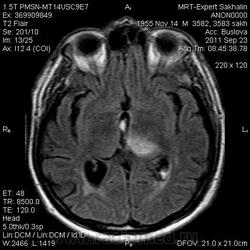

ID:53258

Онмк по геморрагичесому типу с образованием внутримозговой гематомы (подострая аза), прорывом в полость левого бокового и III -го желудочков.

по дате онмк - острая фаза.

И почему острая фаза?Подострый период.

Да, подострый, не знаю куда я смотрел, что насчитал менее 3 дней.